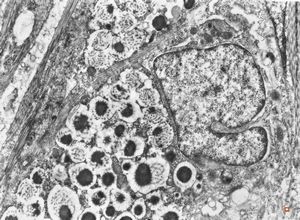

F,38y. | ovary - adenocarcinoma